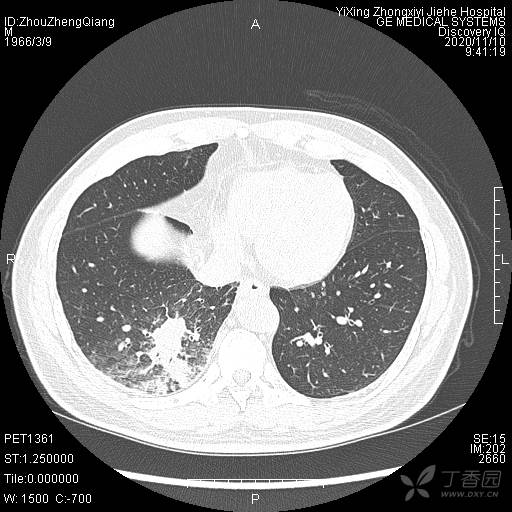

简要病史:咳嗽、咳痰,体重减轻5Kg+。

辅助检查:CT提示:右下肺占位伴周围炎症,CA待排,右侧少许胸腔积液。

临床诊断:右肺癌?待进一步检查。